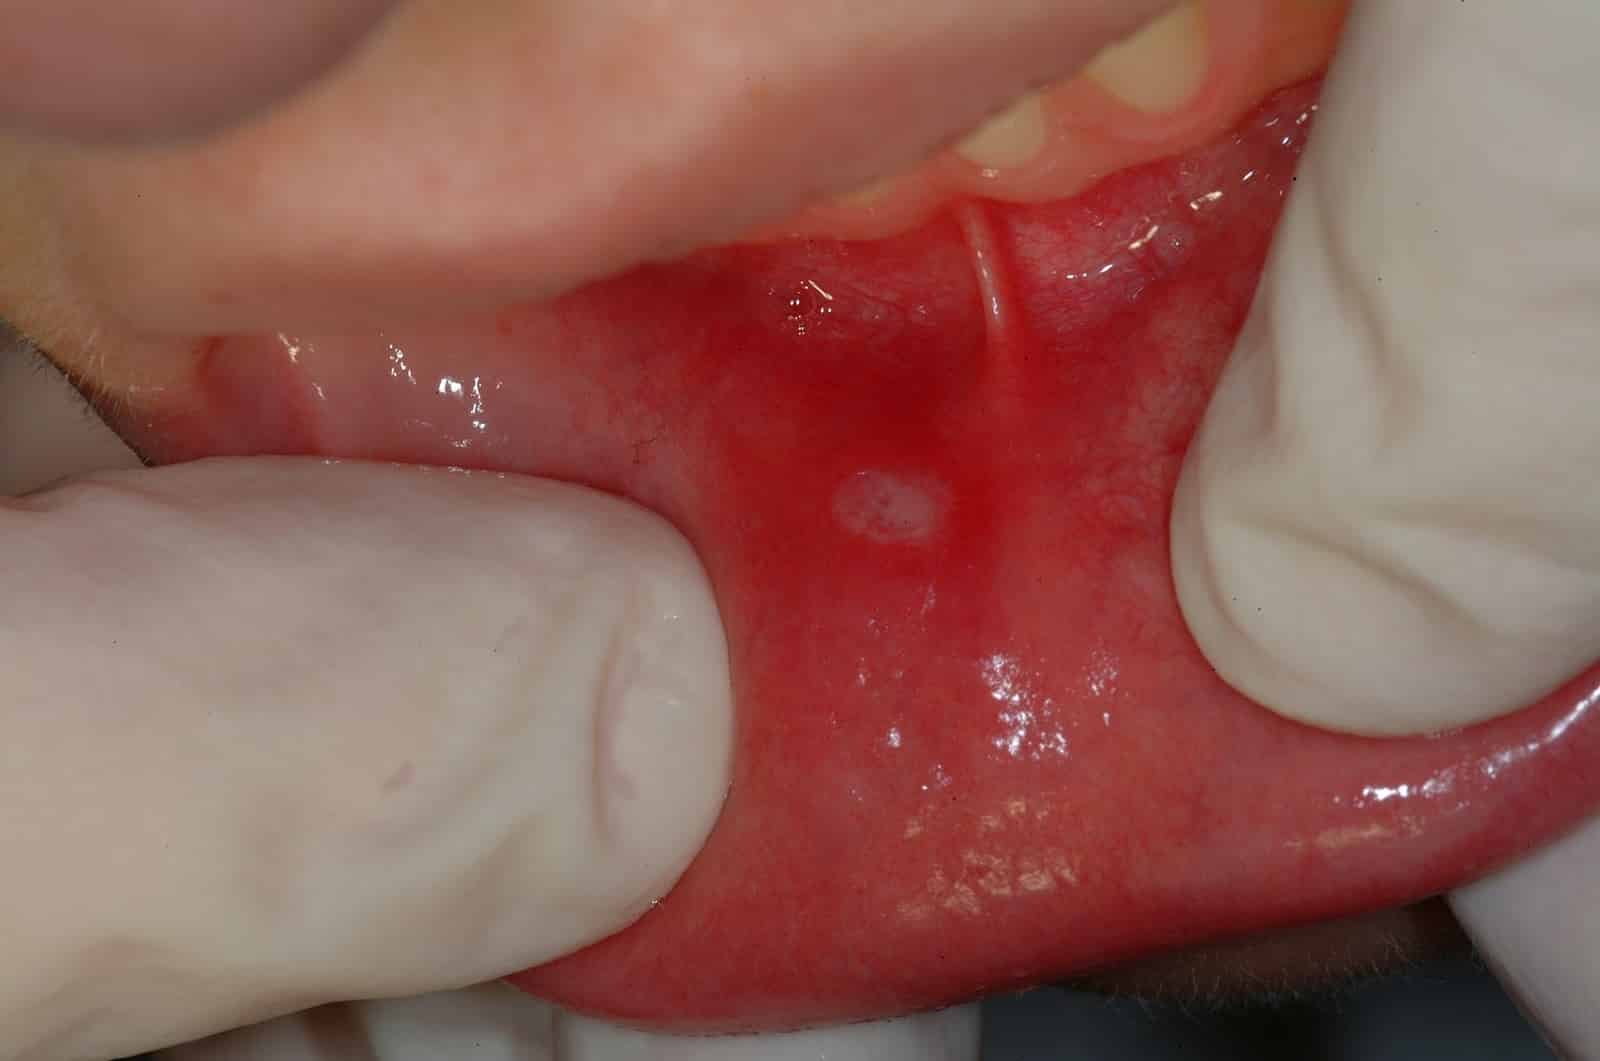

- многочисленные афты, покрытые налетом белесоватого цвета, которые образовались после вскрытия пузырьков герпетических.

- множественные афты на внутренней части нижней губы, которые образовались после вскрытия пузырьков герпетических. Афты на самом кончике языка, на нижней части языка.